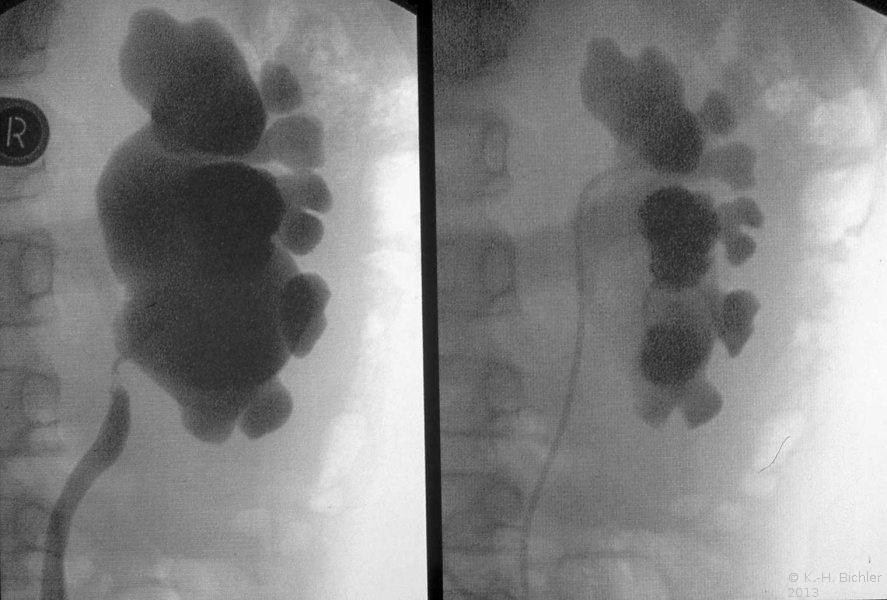

Bei einem fünfjährigen Jungen trat Wochen nach der offenen Pyeloplastik eine Abflussbehinderung auf. Die retrograde Sondierung ergab eine umschriebene Obstruktion. Die in gleicher Sitzung durchgeführte Ballondilatation führte zur Normalisierung der Abflussverhältnisse (Abbildung 15).